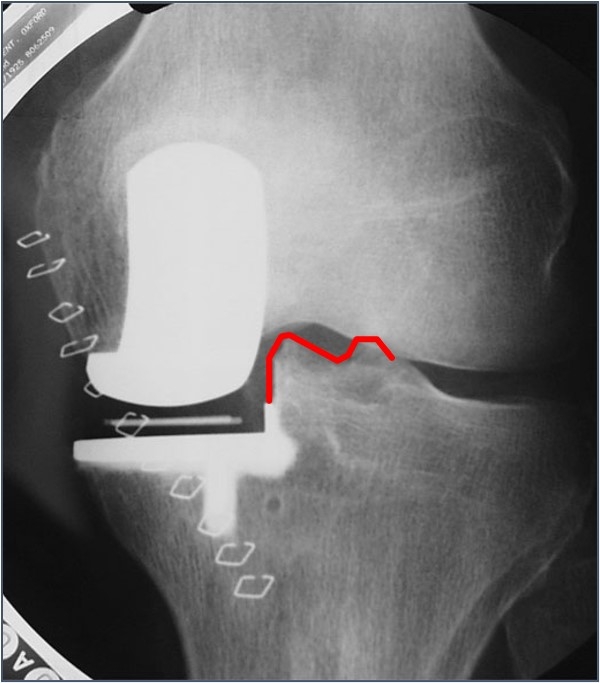

理想的垫片放置于距离外侧1mm,过远易发生垫片旋转脱位,过近易发生撞击。确保垫片不要撞击侧壁,不然—再次截骨。